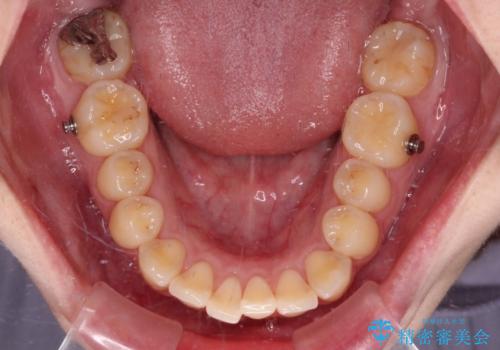

- 矯正装置

- インビザライン

- 前歯のデコボコとクロスバイトが気になり、インビザラインによる矯正治療を希望して来院された患者様です。

上顎側切歯(上の真ん中から2番目の歯)が舌側転位している場合、無理して動かそうとすると歯髄壊死を起こすリスクが高い印象があります。

インビザライン単体でも治療は可能ですが、安全策としてインビザラインで歯列を移動する前に上顎前歯をワイヤー矯正で整え、その後上下歯列をインビザラインにて矯正治療を行うこととしました。